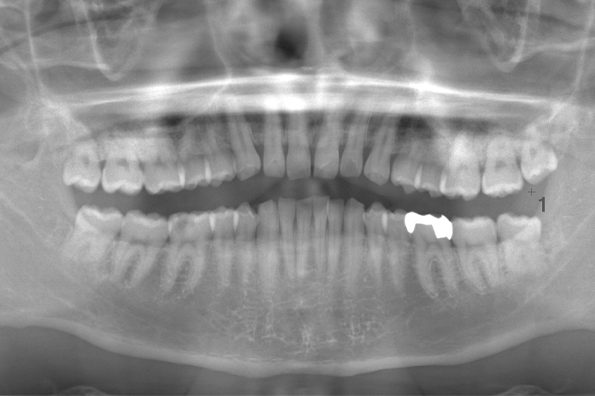

CASE 2

基本情報

| 年齢・性別 | 30代・男性 |

| 主訴 | 左上下親知らず抜きたい |

| 抜歯期間 | 30分 |

| 抜歯費用 | 約2,500円(保険内) 別途CT撮影で3,000円 |

| 抜歯内容 | 左上下の親知らず抜歯 |